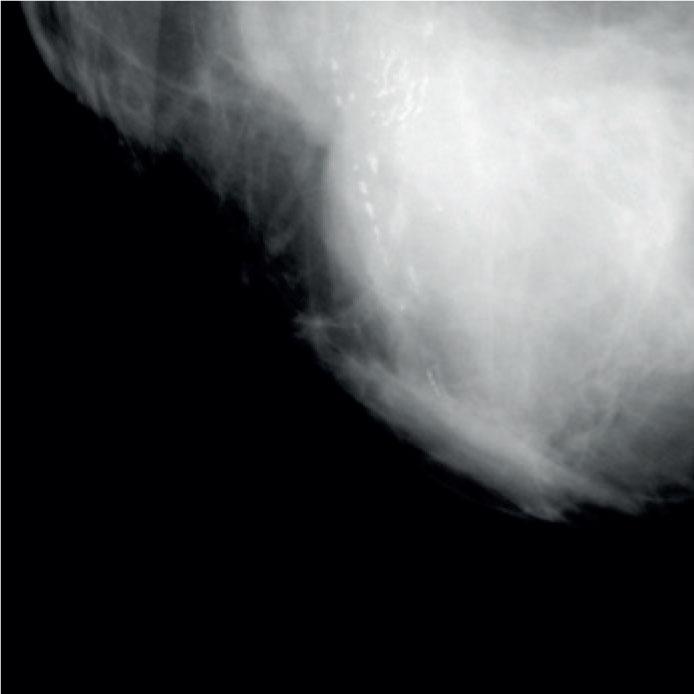

| Microcalcifications type | |

| Powdery | 19 (15) |

| Crushed stone-like | 81 (64) |

| Casting-type | 27 (21) |

| Microcalcifications distribution | |

| Clustered | 85 (67) |

| Grouped | 31 (24) |

| Regional | 11 (9) |